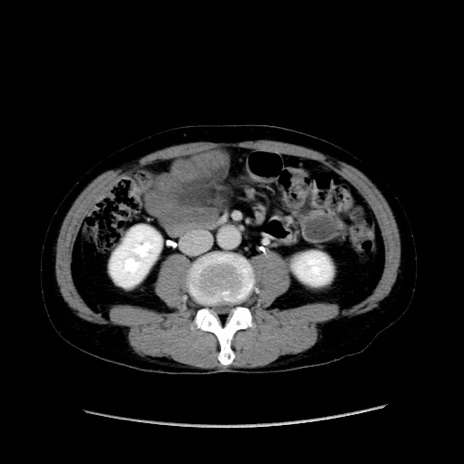

症例37(横断像)

冠状断像

【症例】40歳代 男性

【主訴】腹痛

【現病歴】4時間ほど前に電車に乗車中に臍部上より腹痛出現。徐々に増悪し起立困難となり、救急外来受診。生ものは数日食べていない。今朝お雑煮を食べた。

【身体所見】BT 36.8℃、BP 117/84mmHg、HR 91/min、SpO2 97%、苦悶様、腹部:臍上部広範囲圧痛あり、反跳痛±

【データ】WBC 8100、CRP 0.03